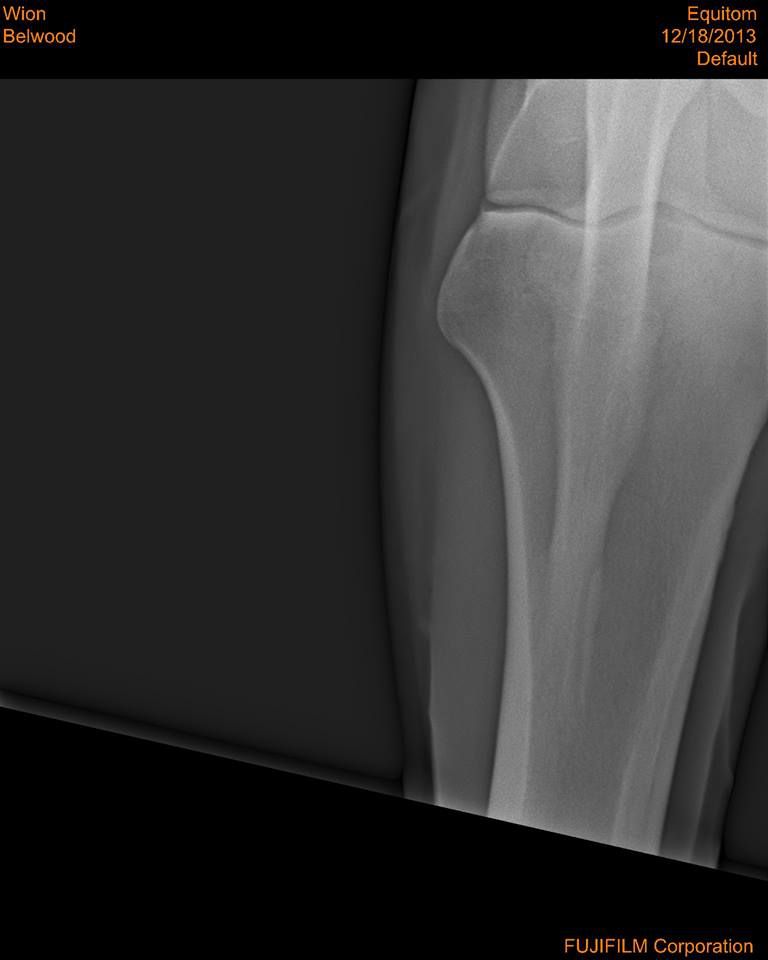

Par conny : le 31/12/13 à 14:11:27

| Dire merci | bon me revoilà avec les radios dites-moi ce que vous en pensez... |

| Dire merci | Je n'y connais pas grand chose, mais il n'y a pas une fracture là où se loge "la boule" de l'articulation ( vers le milieux ) ? Je trouve que c'est bizare à cet endroit... Message édité le 31/12/13 à 14:48 |

| Dire merci | Quercy: je vois ce que tu veux dire mais je suis comme toi, j'y connais rien... nats: comme déjà ecrit, le 1er veto a dit que le cheval n'avait "rien" et le 2eme qu'il fallait l'euthanasier... ici je sais que Al est veto et je pense qu'il doit y en avoir d'autres...donc je prefere voir avec les personnes de confiance, car mon amie ne veut pas euthanasier son cheval et si possible, le donner en tant que tondeuse à gazon... |

| Dire merci | comme déjà ecrit, le 1er veto a dit que le cheval n'avait "rien" et le 2eme qu'il fallait l'euthanasier... Sur les mêmes radio, ces 2 diagnostiques si différents? Et le deuxième véto a forcement commenté les radios avant de proposer l'euthanasie Chez ma jument de 5 ans, le premier véto m'avait aussi dit qu'il n'y avait rien de visible sur les radio malgré le fait qu'elle était positive au test de flexion et lors des radios prises en clinique, il était à (peine) visible qu'il y avait UN bec de perroquet. ça ressemblait un peu à la petite pointe floue à gauche qu'on voit sur ta 2 ème radio, mais bon entre un truc flou anormal et au autre normal... |